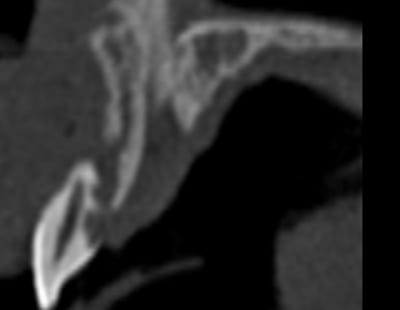

dans le même sujet, j'aurais aimé avoir votre avis sur ce cas. J'hésite entre une ROG avec membrane titane ou une greffe d'apposition.

04/11/2011 à 13h58

et pourquoi pas une expansion? tu as quoi, 14/15mm pour tes 2 implants? du fais 2 prémol? t'as pas besoin de diamètres super important amha...

j'ai 16mm entre les dents, mais 9mm de hauteur de crête pour la 47.

pour ce qui est de l'expansion, je n'ai jamais tenté l'exercice, et les corticales me paraissent bien épaisses.

Faut un peu de temps, mais çà parait pas impossible...

comme les 2 implants sont côte à côte tu bénéficies en plus de la longueur de la tranchée que tu peux faire pour avoir plus de "laxité" ( ou plutôt souplesse de l'os)...et la corticale semble moins dense là où tu as le plus besoin de faire de l'expansion...donc plutôt favorable

2 dents de 8mm çà fait 2 prémo...donc pas besoin d'avoir des implants très larges...des 4mm de diamètre doivent être suffisants...

Dans ce cas de figure, sans aucun doute, Régénération avec vis d'otéosynthèses ( en toile de tente) + membrane osseoguard résorbable.